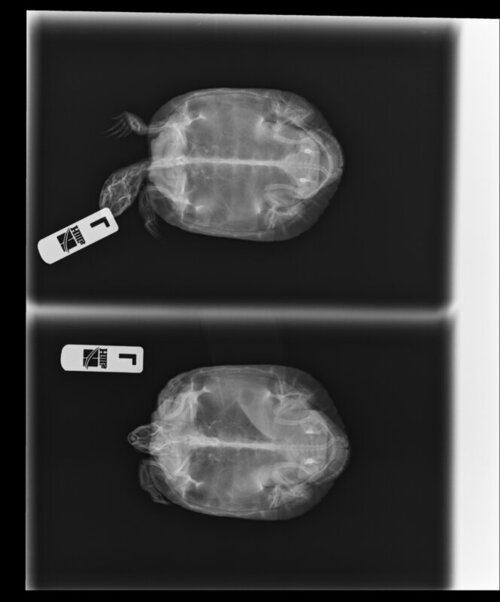

Антон123 Ваше имя: Антон Локация: Москва Опубликовано: 7 апреля 2022 Опубликовано: 7 апреля 2022 1. Москва, 36 2. Красноухая. 3. Содержится в аквариуме Размер жилища большой, в литрах не мерил, см.фото 4. Лампа накаливания в качестве точки прогрева установлена, работает по таймеру с 9 до 21. Ультрафиолетовая лампа UVB10 SimpleZooBulk месяц как менял. Работает с 9 до 21. 4.3. Берег есть 4.4 фильтр для воды, внутренний 4.5. Нагреватель воды установлен 5. Грунта нет 6. Температура воды 26, на бережке под лампой 33 7. Ест 2 раза в неделю, в основном нежирную рыбу. Подкормки есть, но давно не давал 8. Возраст 5-6 лет, вес 370грам, длина панциря 14см В чём проблема/болезнь? Как давно проявилась? Сидит на берегу, чаще всего с закрытыми глазами. Вялая. Состояние такое уже 2-3 недели. Плавает без крена. От еды до сегодняшнего дня не отказывалась. Сегодня уже и ела совсем чуть-чуть и еле-еле. 9. Приезжала врач, рекомендовала сделать рентген, на всякий случай уколола кальций и оставила еще, чтобы мы кололи через день. Рентген приложил здесь, фото всего остального по ссылке ниже 10. https://postimg.cc/gallery/8zGcDFG

Антон123 Ваше имя: Антон Локация: Москва Опубликовано: 7 апреля 2022 Автор Опубликовано: 7 апреля 2022 (изменено) А нет. Шприц на 1мл. 50 делений. Вот 2,5 таких деления. Получается 0,02*2,5=0,05 И! Забыл написать в самом начале. Пару дней назад черепаха зависла не шевелясь в воде с открытым ртом и так и висела. А когда доставал ее на сушу, она бодро бежала назад в воду. И было ощущение, что она не может уходить на дно Также на самом нижнем рентгеновском снимке мне кажется что-то не то в нижней части черепахи. Изменено 7 апреля 2022 пользователем Антон123

Консультанты moth Ваше имя: Мария Локация: Москва Опубликовано: 8 апреля 2022 Консультанты Опубликовано: 8 апреля 2022 @Антон123 пока нет по этим снимкам нельзя понять есть проблемы с лёгкими или нет, нужны другие проекции